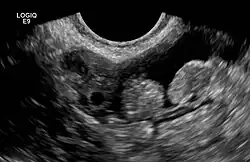

In seltenen Fällen kann es zu einer Verdrehung (Torsion) und zu einer Infarzierung dieser Anhängsel kommen, die dann schmerzhaft ist und je nach Lage der betroffenen Appendix mit einer normalen Appendizitis oder auch mit einer Sigmadivertikulitis verwechselt werden kann.[2] Man spricht dann von einer Appendicitis epiploica. Im englischen Sprachraum wird auch von einer Epiploic appendagitis[3] gesprochen, um eine Verwechslung mit der Appendizitis des Wurmfortsatzes zu vermeiden.